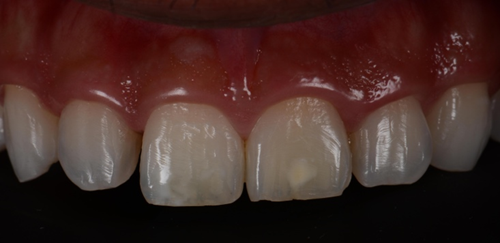

This 22-year-old male came to the clinic complaining of pain and esthetic dissatisfaction following orthodontic treatment. The patient said that his orthodontic treatment lasted more than 4 years. Upon clinical examination, the patient presented with mild to moderate post orthodontic white spot lesions (WSL) affecting the two upper central incisors. Tooth #21 exhibited yellowish discoloration compared to the adjacent teeth due to calcific metamorphosis (Figure 1).

Figure 1. Preoperative frontal photo with a black background to make the contrast better and the white spots more clear